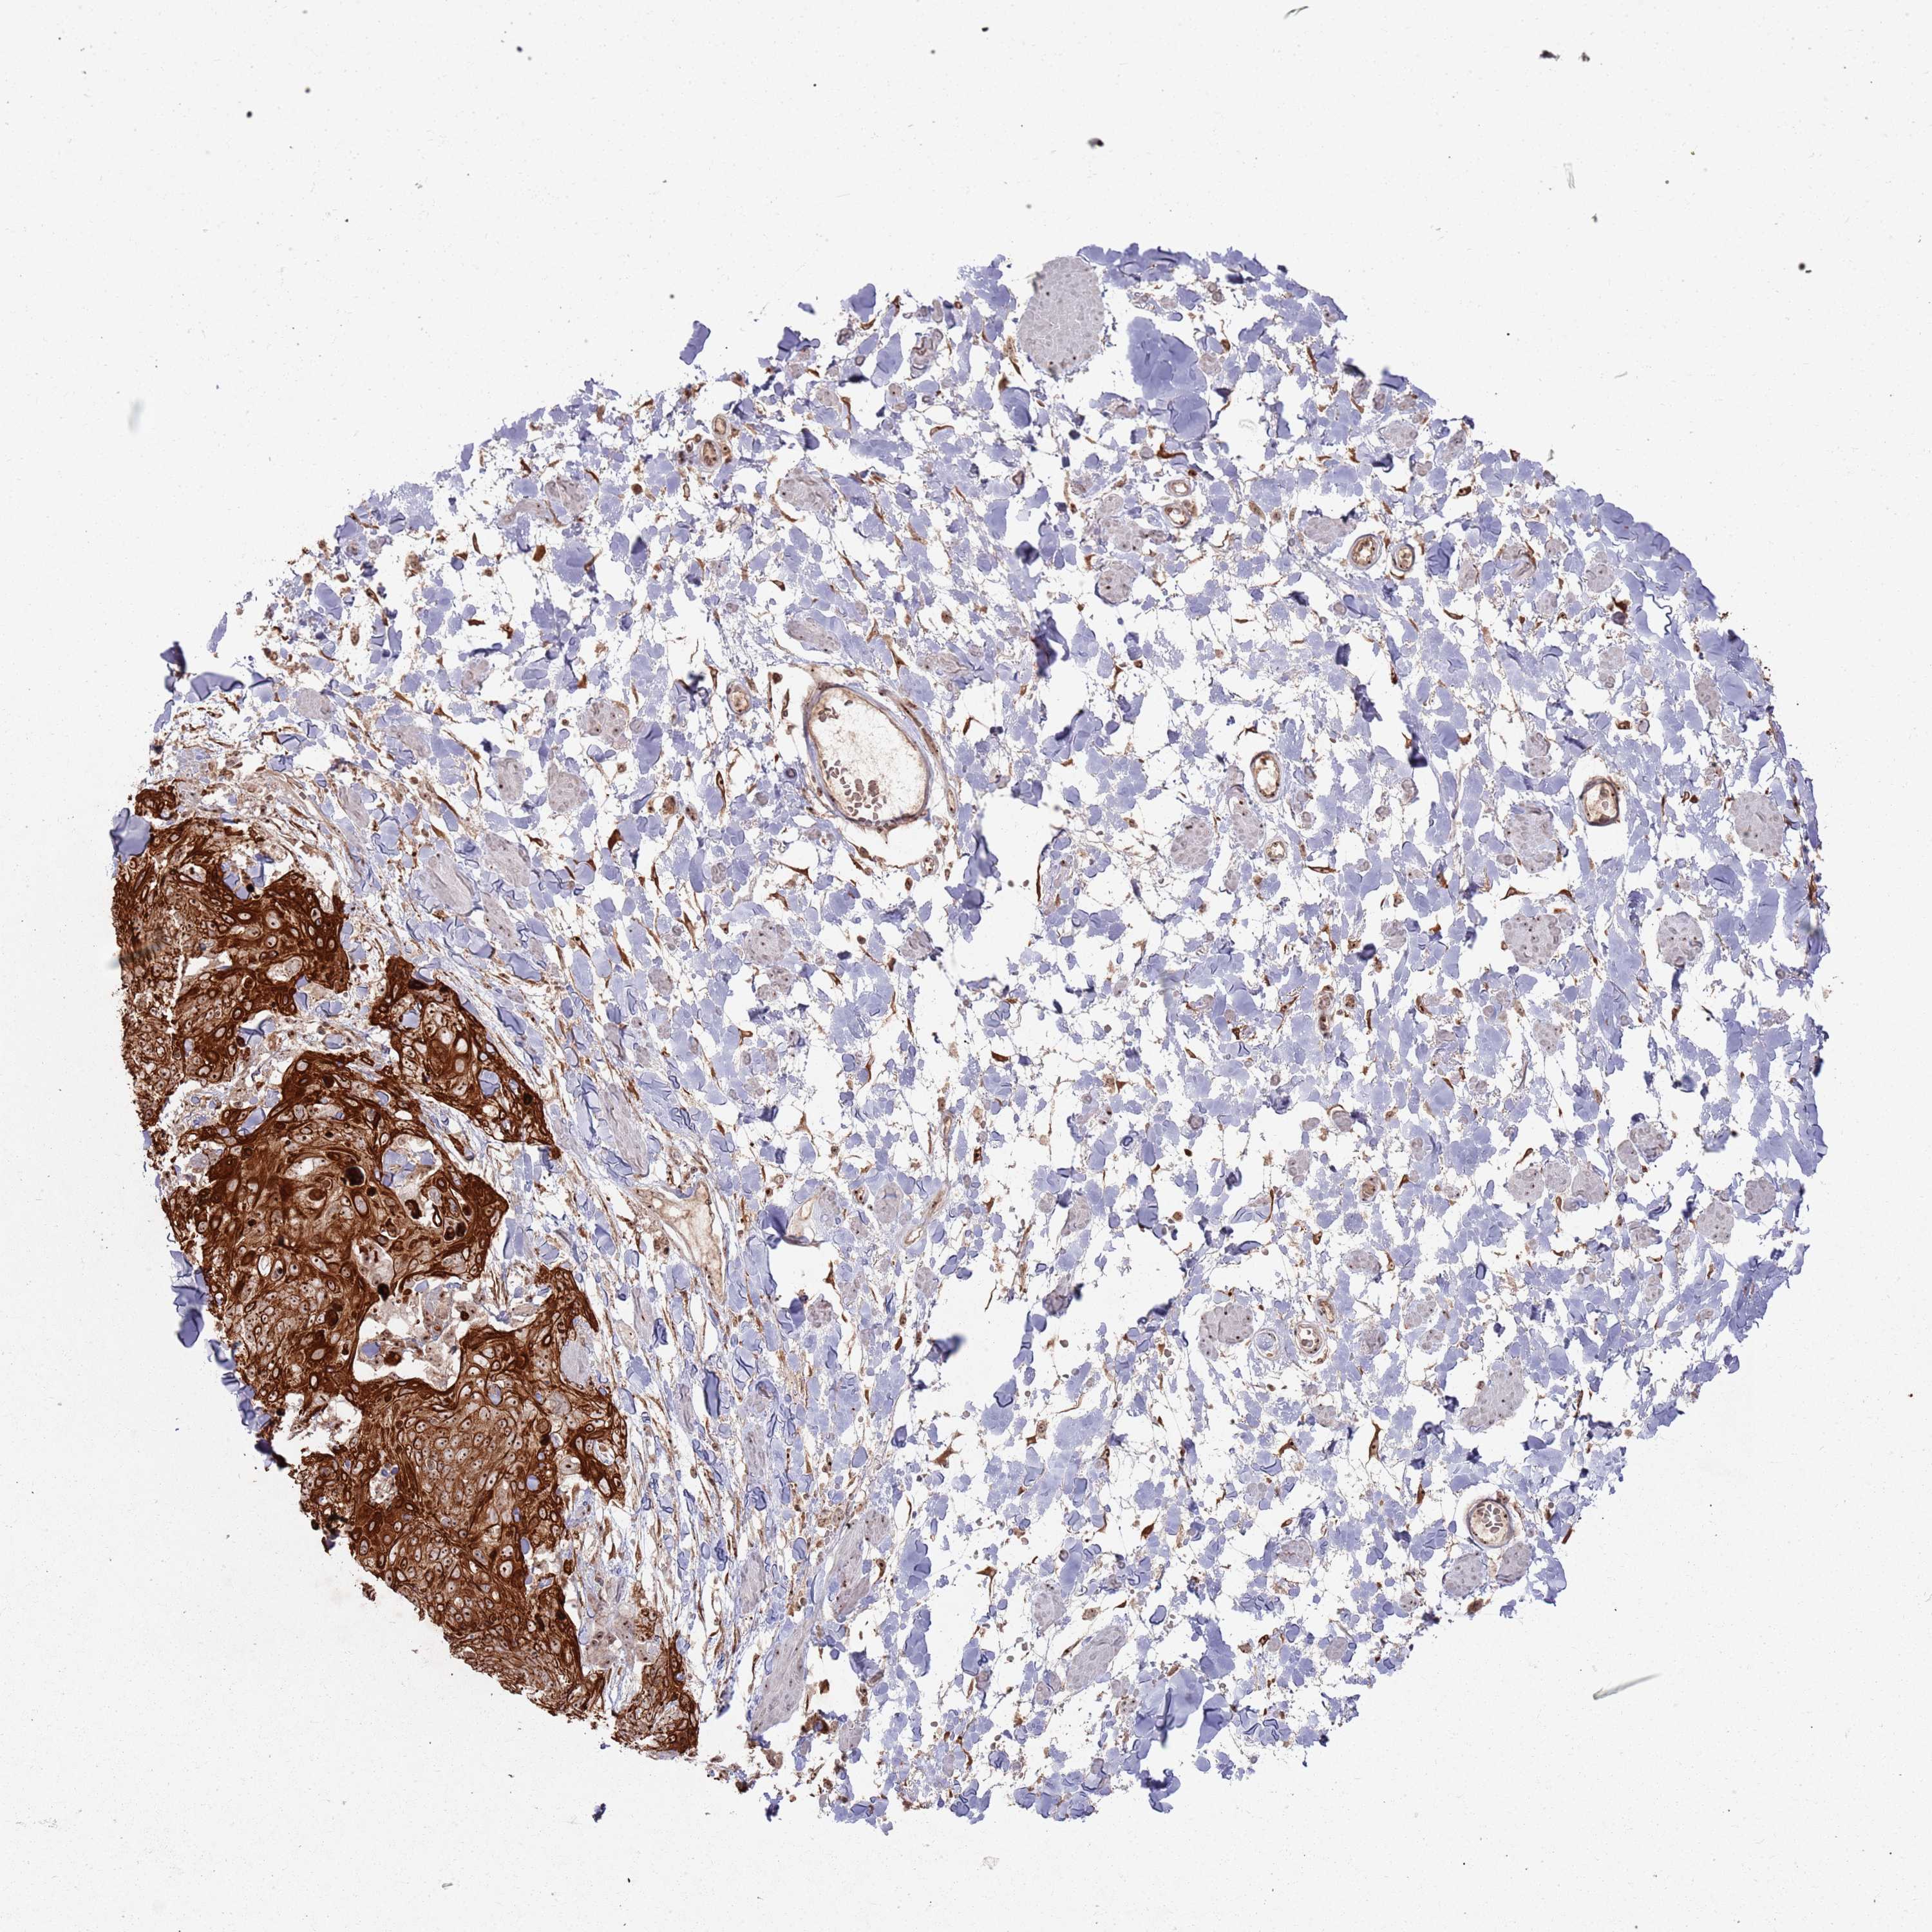

SKIN CANCER - Protein expressioni

A mouse-over function shows sample information and annotation data. Click on an image to view it in a full screen mode. Samples can be filtered based on level of antibody staining by selecting one or several of the following categories: high, medium, low and not detected. The assay and annotation is described here.

Antibody stainingi

Antibody staining in the annotated cell types in the current human tissue is reported as not detected, low, medium, or high, based on conventional immunohistochemistry profiling in selected tissues. This score is based on the combination of the staining intensity and fraction of stained cells.

Each image is clickable and will lead to virtual microscopy that enables deeper exploration of all samples and also displays staining intensity scores, fraction scores and subcellular localization as well as patient and tissue information for each sample.

Antibody HPA045830

Staining

High

Medium

Low

Not detected

Intensity

Strong

Moderate

Weak

Negative

Quantity

>75%

75%-25%

<25%

None

Location

Nuclear

Cytoplasmic/membranous

Cytoplasmic/membranous,nuclear

Basal cell carcinoma

Squamous cell carcinoma, NOS

Squamous cell carcinoma, metastatic, NOS

Squamous cell carcinoma in situ, NOS